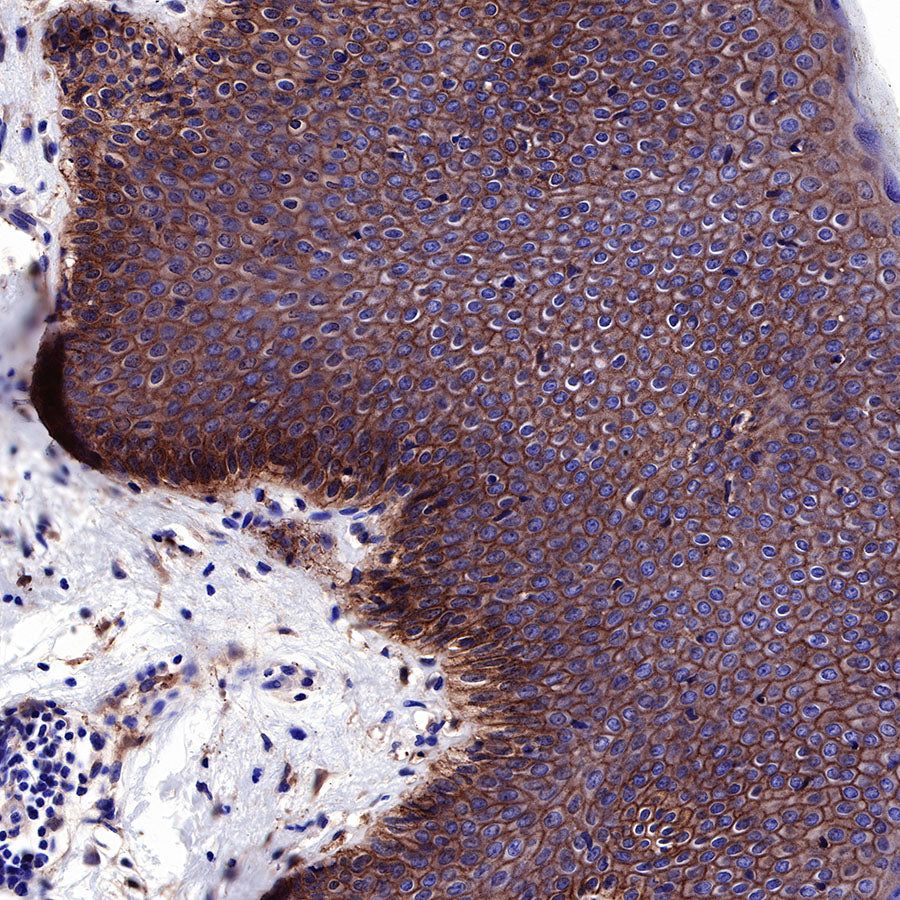

IHC shows positive staining in paraffin-embedded human colon. Anti-EGFR antibody was used at 1/2000 dilution, followed by a HRP Polymer for Mouse & Rabbit IgG (ready to use). Counterstained with hematoxylin. Heat mediated antigen retrieval with Tris/EDTA buffer pH9.0 was performed before commencing with IHC staining protocol.

IHC shows positive staining in paraffin-embedded human esophagus. Anti-EGFR antibody was used at 1/2000 dilution, followed by a HRP Polymer for Mouse & Rabbit IgG (ready to use). Counterstained with hematoxylin. Heat mediated antigen retrieval with Tris/EDTA buffer pH9.0 was performed before commencing with IHC staining protocol.

IHC shows positive staining in paraffin-embedded human placenta. Anti-EGFR antibody was used at 1/2000 dilution, followed by a HRP Polymer for Mouse & Rabbit IgG (ready to use). Counterstained with hematoxylin. Heat mediated antigen retrieval with Tris/EDTA buffer pH9.0 was performed before commencing with IHC staining protocol.

IHC shows positive staining in paraffin-embedded human skin. Anti-EGFR antibody was used at 1/2000 dilution, followed by a HRP Polymer for Mouse & Rabbit IgG (ready to use). Counterstained with hematoxylin. Heat mediated antigen retrieval with Tris/EDTA buffer pH9.0 was performed before commencing with IHC staining protocol.